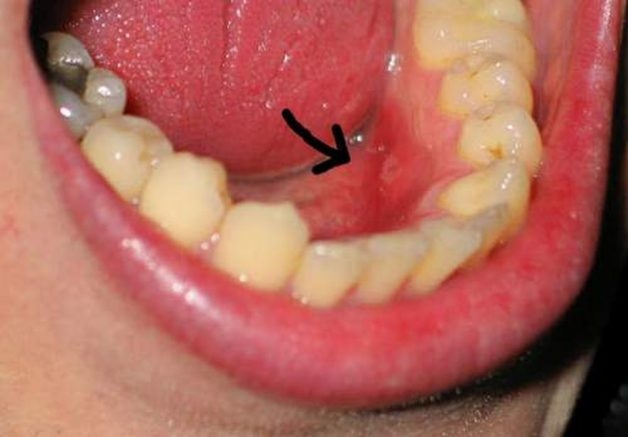

Đây là tình trạng phần lợi ở phía trong hàm bao phủ lên bề mặt răng khôn, khiến răng khôn bị kẹt và khó phát triển. Khi phần răng khôn mọc thêm sẽ đâm vào phần lợi, khiến người bệnh cảm thấy đau đớn và khó chịu. Nếu không được điều trị kịp thời, bệnh lý này có thể gây những hệ lụy nghiêm trọng đến sức khỏe răng miệng.

Viêm lợi trùm răng khôn là tình trạng phần lợi ở phía trong hàm bao phủ lên bề mặt răng khôn, khiến răng khôn bị kẹt và khó phát triển.

3.1 Lợi bị sưng

– Phần lợi có màu đỏ và sưng phồng lên thành bọng lớn. Khi dùng tay ấn vào lợi, bạn sẽ có cảm giác đau đớn. Một số trường hợp có thể thấy có nước và mủ chảy ra.